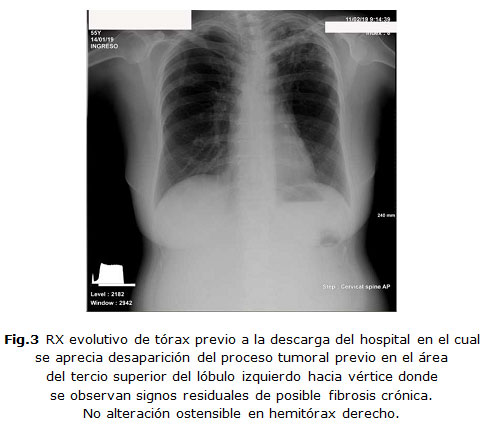

La evolución de la paciente ha sido muy positiva desde el punto de vista clínico y radiológico (Figura 3)  con regresión de toda la sintomatología, los resultados de los exámenes complementarios evolutivamente y de la  imagen radiológica,  que llegó a borrar las lesiones antes reportadas completamente.  Se decidió el alta hospitalaria luego de 30 días de su ingreso. Continúa con el protocolo de tratamiento de su enfermedad por consultas externas con 60 mg de prednisona oral en régimen de descenso, y bolos mensuales de ciclofosfamida hasta la inducción, luego de los cuales se proseguirá  con drogas citotóxicas como terapia de mantenimiento y con  seguimiento por  la Especialidad de Reumatología y Medicina Interna.